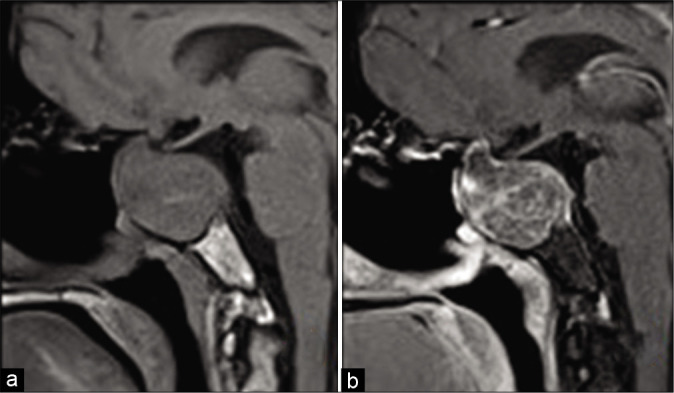

一名49歲的女性被轉(zhuǎn)介到醫(yī)院作為一個(gè)大型無(wú)癥狀垂體大腺瘤的病例進(jìn)行外科治療。在多方位的臨床評(píng)估中,患者報(bào)告稱,在過(guò)去的2年中,她一直抱怨慢性雙顳頭痛、原因不明的易疲勞性和緩慢的進(jìn)行性視力下降。她還報(bào)告說(shuō)患有高血壓,通過(guò)藥物治療可以得到充分控制。她報(bào)告沒有任何外科手術(shù)史或任何家族性疾病。檢查時(shí),除了視力問題外,顱神經(jīng)評(píng)估并不。詳細(xì)的眼科檢查顯示雙眼視力下降,更多在左側(cè),伴有雙顳同向偏盲。內(nèi)分泌評(píng)估和生化檢查顯示中樞性甲狀腺功能減退,可通過(guò)左旋甲狀腺素替代療法進(jìn)行治療。大腦的計(jì)算機(jī)地形圖成像顯示一個(gè)稍高密度的大型鞍/鞍上腫塊,向兩側(cè)海綿竇延伸,右側(cè)鞍旁延伸。病變擴(kuò)大了骨蝶鞍,伴有上斜坡的凹陷和重塑【圖1】。

靜脈注射造影劑的鞍區(qū)磁共振成像顯示鞍區(qū)/鞍上/鞍旁較大腫塊,T1圖像呈不均勻低信號(hào),T2圖像呈中等高信號(hào),DWI圖像呈中央小面積擴(kuò)散限制,增強(qiáng)后呈輕度斑片狀強(qiáng)化。它的前后、頭尾部和橫向尺寸分別約為36x41x50 mm。病變完全包裹右側(cè)頸內(nèi)動(dòng)脈海綿竇段和床突段,部分包裹右側(cè)床突上段和左側(cè)海綿竇段。病變還對(duì)鄰近的結(jié)構(gòu)產(chǎn)生腫塊效應(yīng),表現(xiàn)為腫瘤隆起和三腦室底,視神經(jīng)和視交叉的顱內(nèi)段被拉伸并與病變分離。垂體和垂體柄看不見【圖2】。

圖2:術(shù)前核磁共振圖像。(a)冠狀面T1,(b)矢狀面T1,(c)冠狀面T2,(d)冠狀面后對(duì)比,(e)矢狀面后對(duì)比,(f)病變的軸位DWI圖像顯示不均勻的低T1信號(hào)、中高T2信號(hào)、斑片狀后對(duì)比增強(qiáng),中央?yún)^(qū)域擴(kuò)散受限。

術(shù)后期間的臨床再評(píng)估顯示患者的視力和視野有明顯好轉(zhuǎn)。隨訪MRI顯示視交叉和神經(jīng)充分減壓,盡管鞍內(nèi)有大的殘余病變[圖4]。

圖4:術(shù)后核磁共振圖像。(a)矢狀位對(duì)比前圖像和(b)對(duì)比后T1加權(quán)圖像,顯示盡管存在較大殘留鞍區(qū)海綿狀血管瘤,但術(shù)后即刻的磁共振圖像顯示視神經(jīng)充分減壓